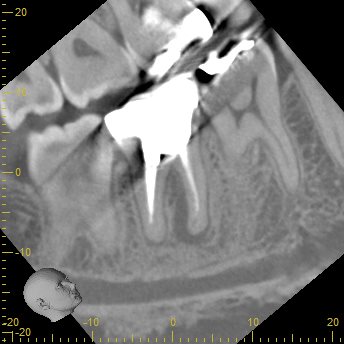

CBCT(2023.12.20)

MB

根切するには厳しい位置に#31のM根のApexはある。

穿通は必須である。